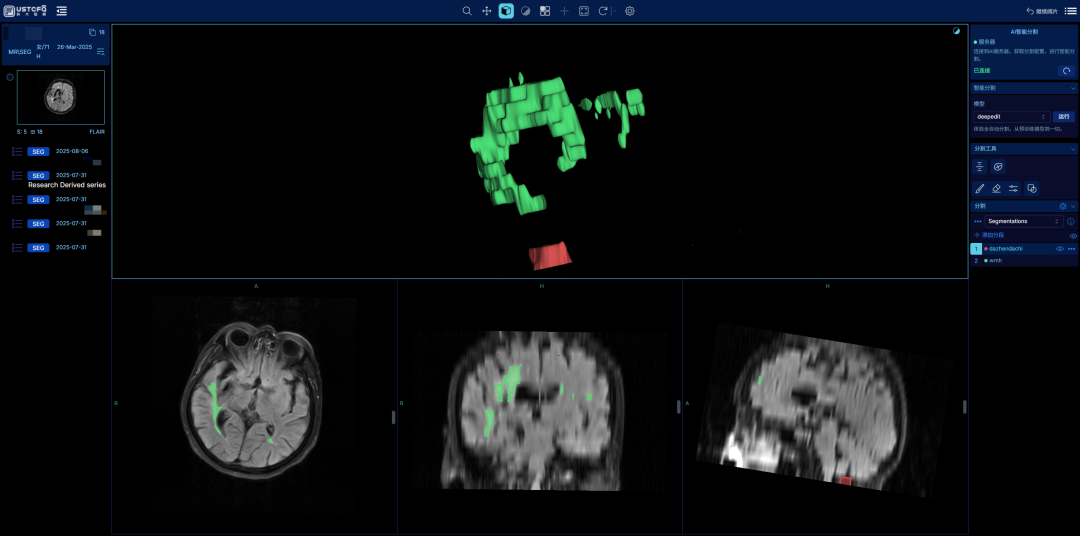

4、用户将视图调成3D模式下,渲染预设,能更清晰地看到三维区域。

.png)